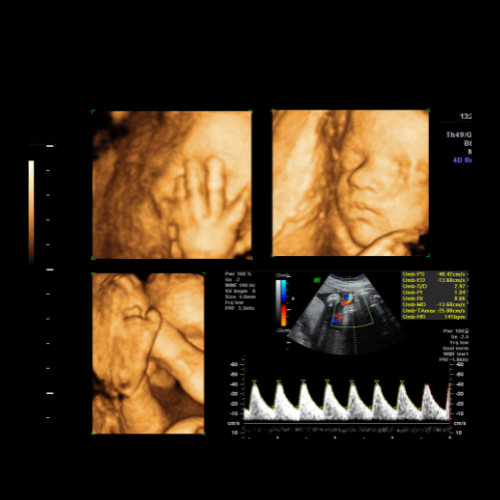

Fetal Growth Scan (28–32 Weeks GA)

Your Complete Guide to Fetal 3D/4d Growth Scan in Kolkata at NESA Institute of Fetal Medicine Are you looking for